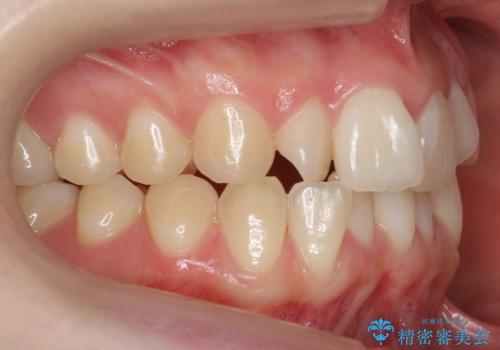

- 前歯のねじれを主訴に来院。

前から2番目の歯がねじれて下の歯の内側に入っていました。

また、奥歯のかみ合わせが上の奥歯が若干前に並んでおり、それで前歯が入りきらずにねじれていました。

歯を抜かずに奥歯を後ろに下げてマウスピースで矯正しています。

上の奥歯を後ろに下げて前歯のねじれを治すスペースを確保しました。

奥歯を後ろに下げるために、矯正用インプラントを使用しています。